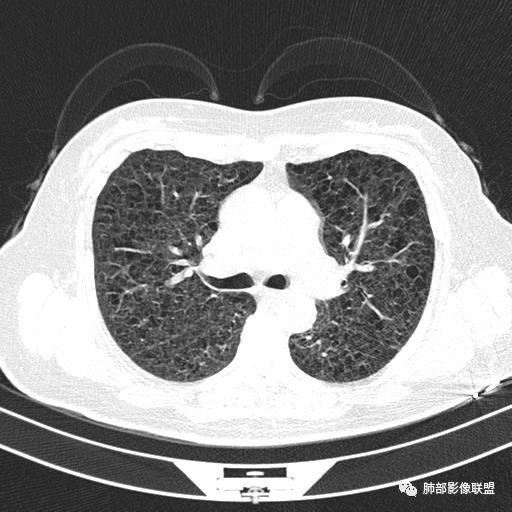

双肺弥漫囊腔,累及肋膈角,囊腔形态相对规则单一。

CT平扫示双肺弥漫分布大小不等囊状薄壁透光区,无内、中、外带分布差异,间质稍示增厚。拟LAM

中年女性育龄期妇女,咳嗽气喘,无吸烟史,有苯吸入史。影像:双肺弥漫均匀小囊腔,无明显分布优势,囊腔形态欠规则,壁薄,部分囊腔边缘血管征,伴双肺弥漫磨玻璃影,无结节,考虑lam,鉴别苯中毒肺损伤,囊腔多有分布优势,小叶中心分布为主,形态规整等

CT表现:双肺弥漫大小不等的薄壁囊腔,囊壁<2mm,外形规则,血管影多位于囊腔周围,囊腔之间肺组织正常,随着疾病进展到晚期,囊腔变大、增多,不可胜数,囊腔可融合成较大的囊,与肺气肿相似,形成间质性肺纤维化。部分病例可出现结节影。